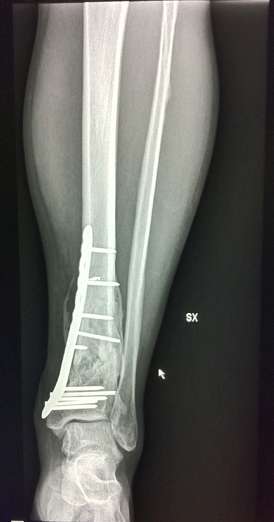

Seconda operazione: rimozione placca rotta e "montaggio" nuova placca:

Nuova placca

[​IMG]

[​IMG][​IMG]

La prima operazione è stata nel 04/2010 (prima piastra)

La seconda nel 10/2010 (sostituzione piastra)

La terza nel 04/2012 (rimozione seconda piastra)